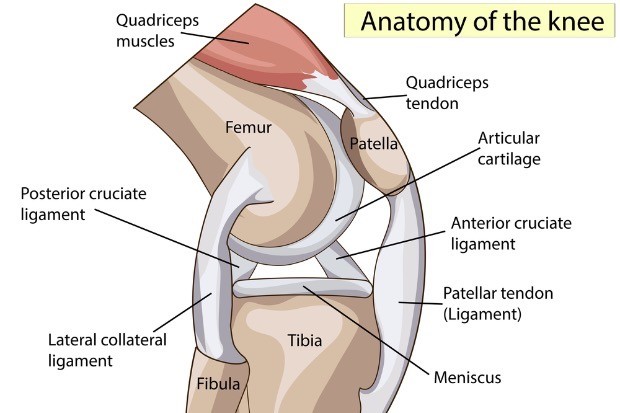

무릎은 체중을 오롯이 지탱하며, 커다란 가동범위를 확보하기 위해 매우 불안정한 구조를 형성하고 있는 관절이다. 허벅지 뼈인 대퇴골과 정강이 뼈인 경골 그리고 무릎뚜껑 뼈인 슬개골 3개의 뼈로 구성되어 있다.

각각의 뼈의 면에는 관절의 마찰을 줄이기 위해 부드러운 연골이 둘러싸여 있다. 2-3mm 두께로 구성되어 있으며, 이러한 연골이 없다면 관절은 충격에 취약해지고, 운동도 매끄럽지 못하게 된다.

한편 무릎이 감당해야 하는 체중이 엄청나다보니, 연골 사이에 서스펜션과 같은 구조가 한가지 더 존재한다. 이를 연골판이라 하는데, 반달처럼 생겼다하여 반월상연골판이라 부른다. 내측에 하나 외측에 하나 자리를 잡고서 관절의 안정성을 유지하고 충격흡수 및 압력을 분산하는 일을 한다.

한편 관절의 안정성을 부여하기 위한 또 다른 구조물이 있는데, 바로 늘 병원에서 늘어났다는 이야기를 듣는 인대이다. 관절면 중앙부에 전방, 후방 십자인대가 있고, 관절의 측면을 감싸는 측부인대가 관절을 지지해준다.